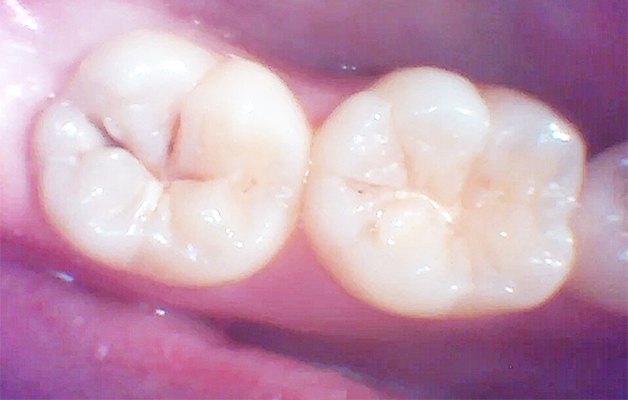

上記は、保険内治療でレジン充填治療(白い詰め物治療)を行った時の写真です。

治療時は口腔内カメラを活用し、治療前、治療中、治療後の状態を出来るだけ分かりやすくお伝えしています。